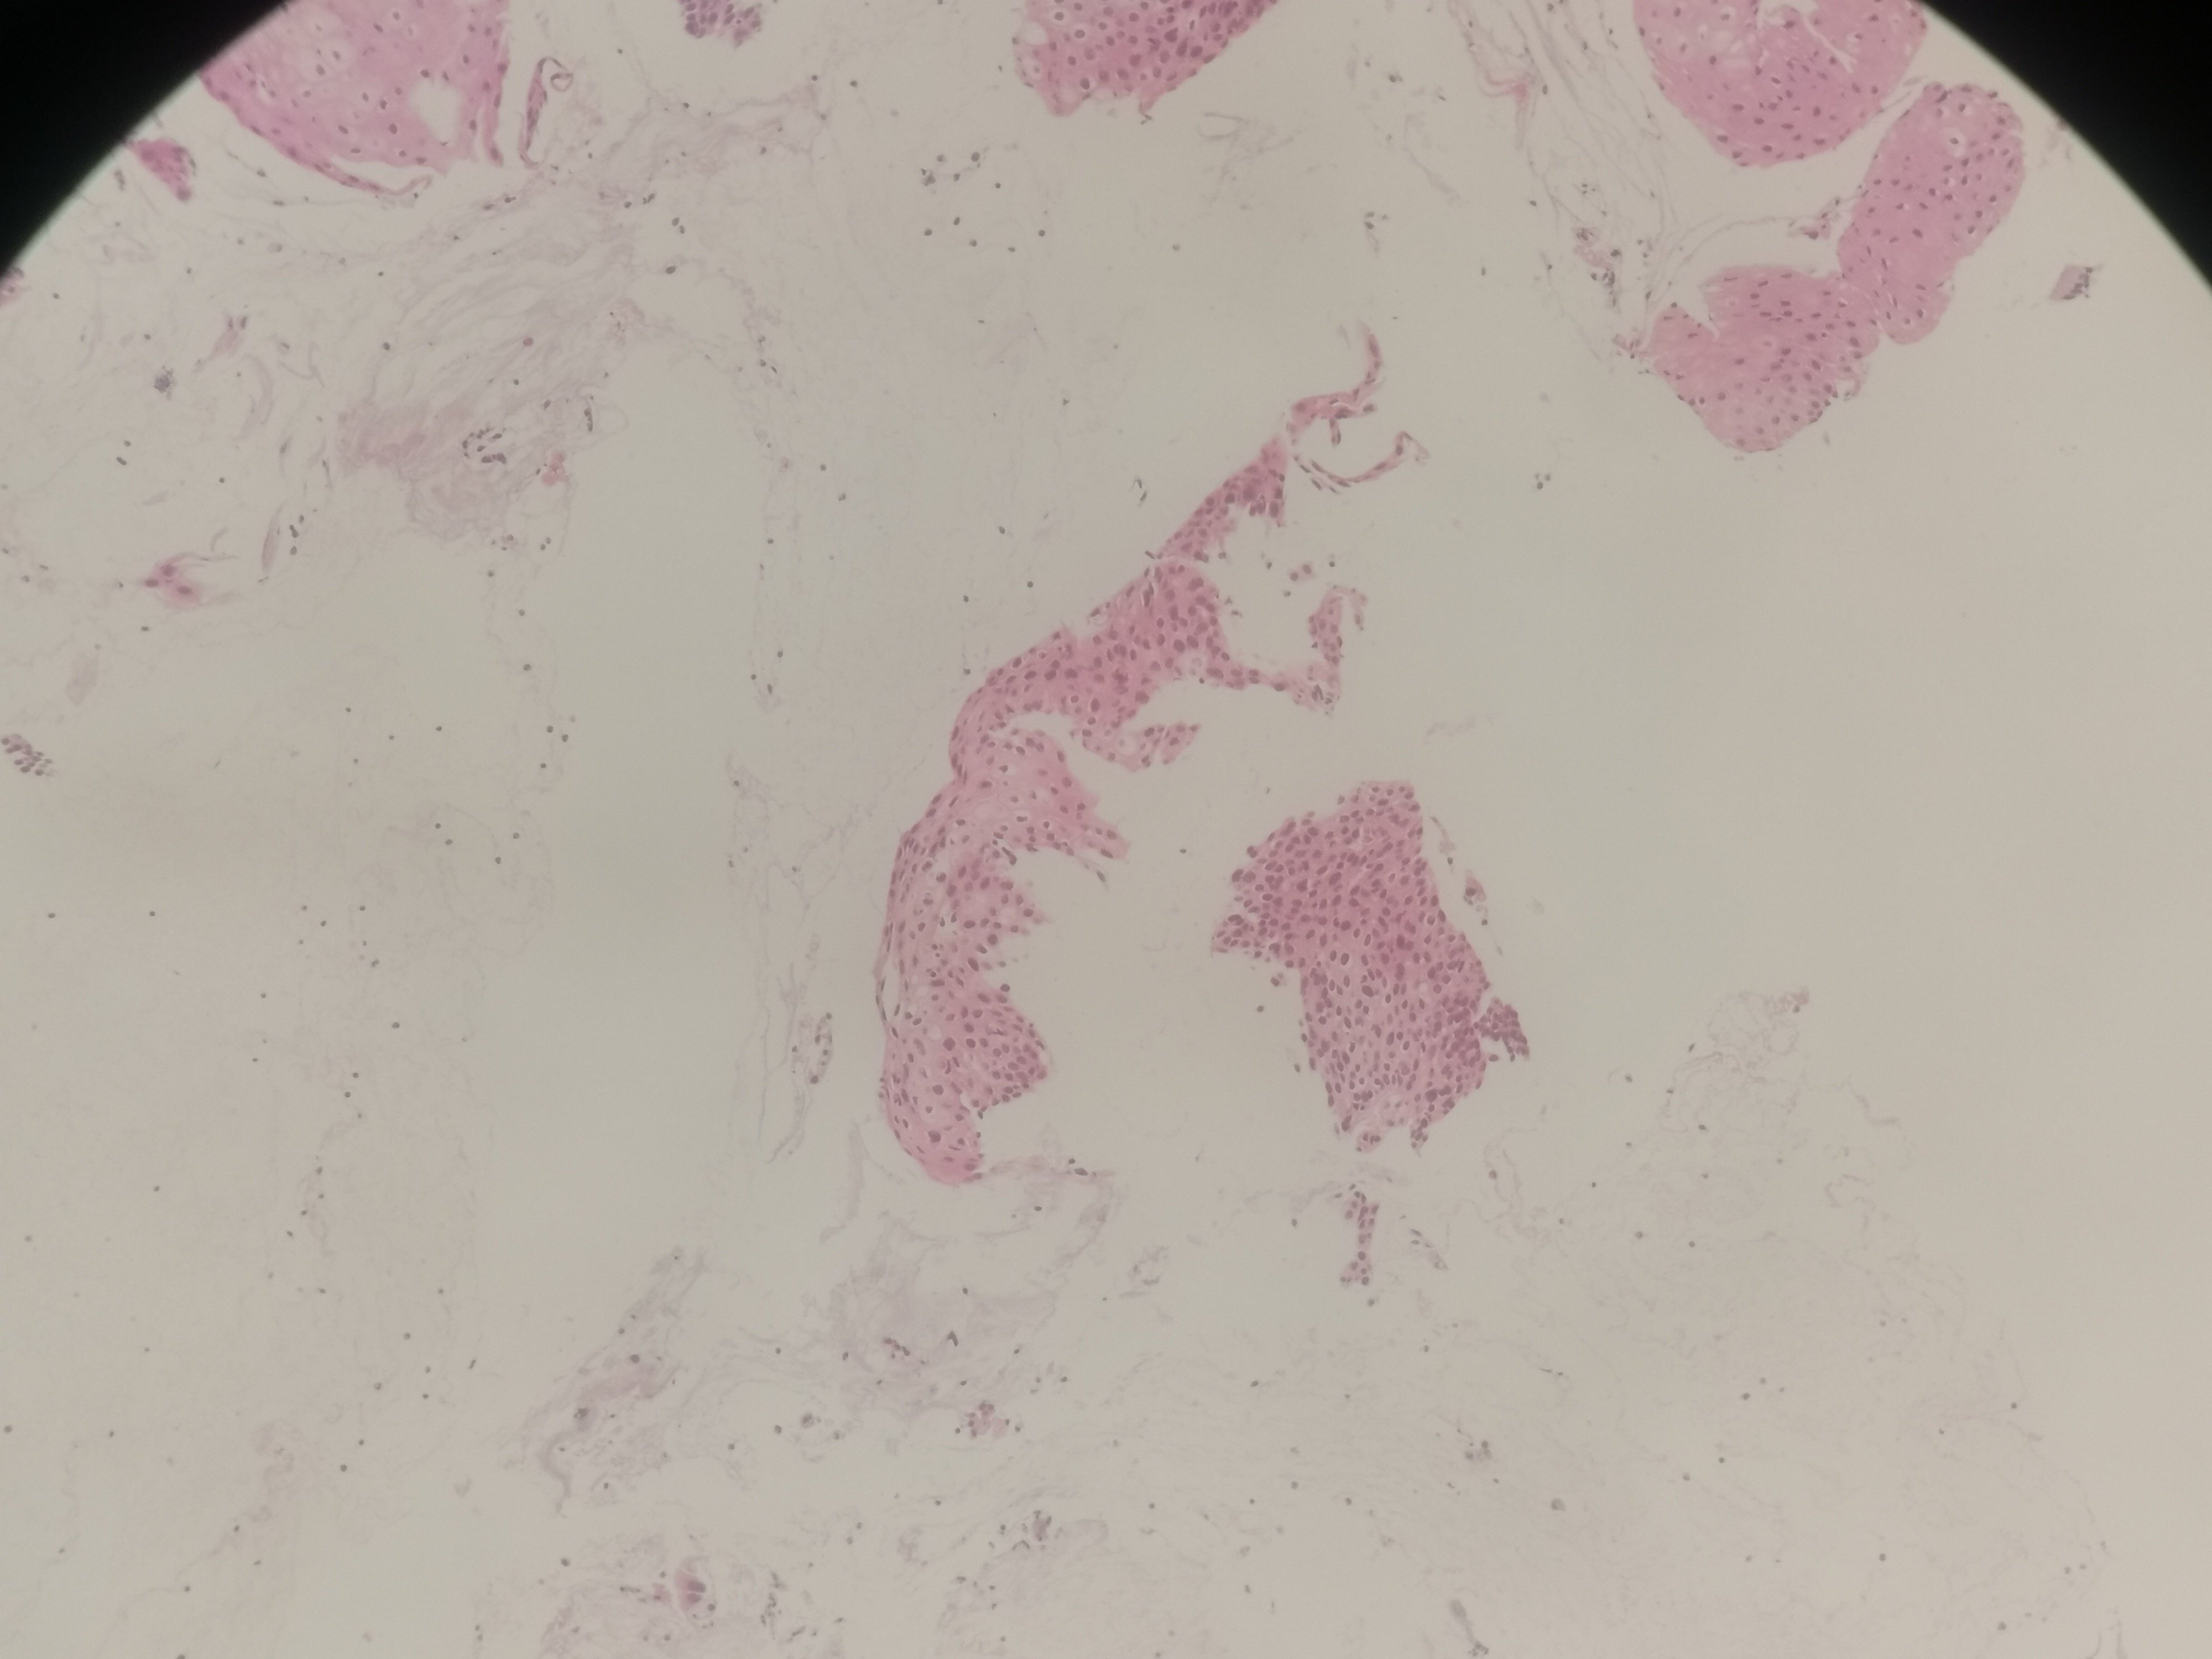

急!请老师帮忙看看,12点够CINii吗,还是报CINI~II

性别

女

年龄

59岁

临床诊断

HPV感染

一般病史

HPV16(+)

标本名称

宫颈活检组织

大体所见

3点:0.8x0.4x0.3厘米1块。6点0.7x0.6x0.3厘米1块。9点0.6x0.6x0.4厘米1块。12点0.8x0.5x0.3厘米,0.6x0.6x0.4厘米2块。

图1~16为12点2块组织,图17为9点组织,图18,为6点组织,图19为3点组织。

倾向低级别,标记看看